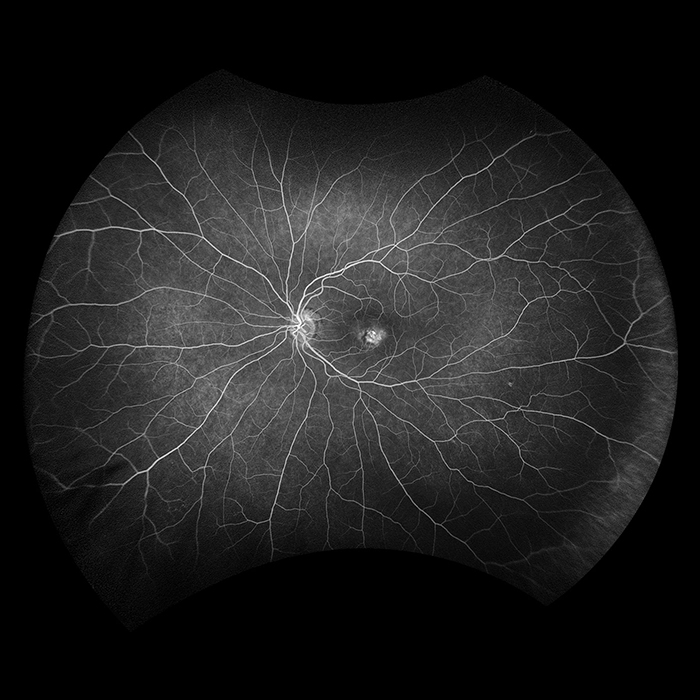

Daytona

Daytona produces a 200° single shot optomap retinal image of unrivaled clarity in less than ½ second. This fast, easy, patient-friendly, ultra-widefield imaging technology was designed for healthy eye screening and has been shown to improve practice flow and patient engagement.

Why Daytona?

optomap has been shown to enhance pathology detection and disease management and to improve clinic flow. The Daytona system is the most widely used true UWF imaging device.

optomap Image Modalities

- color rg

- Sensory Retina

- Choroidal

- green af